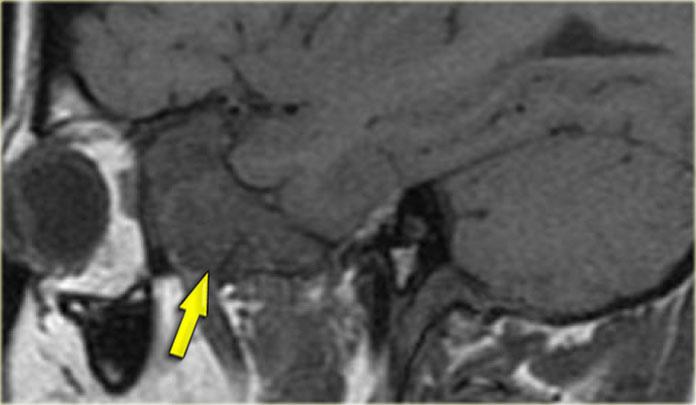

Bên trái là hình ảnh CT của một bệnh nhân sau ghép phổi có sốt và liệt nhiều dây thần kinh sọ tiến triển nhanh.

Chúng tôi sẽ trình bày hình ảnh CT và MRI của bệnh nhân này. Chẩn đoán u lympho được xác định qua sinh thiết.

Trước tiên hãy nghiên cứu các hình ảnh để đánh giá mức độ lan rộng của bệnh.

Sau đó tiếp tục đọc.

Trên hình ảnh CT, các phát hiện bao gồm:

- Khối mô mềm trong xoang hàm (mũi tên đỏ).

- Phá hủy thành xoang (mũi tên vàng).

- Tái cấu trúc và phá hủy xương chân bướm (mũi tên xanh dương).

- Khối mô mềm lớn trong khoang cơ nhai (dấu hoa thị).

Hình ảnh bên phải ở mức cao hơn.

Có hình ảnh mờ đục xoang bướm kèm phá hủy và loãng xương bướm.

CT thể hiện rõ sự phá hủy xương và một phần xâm lấn mô mềm.

Tiếp tục xem hình ảnh MRI.

Bên trái là hình ảnh MRI tương ứng.

Trước tiên hãy nghiên cứu các hình ảnh, sau đó tiếp tục đọc.

Các phát hiện bao gồm:

- Dịch trong xoang bướm phải (mũi tên đỏ).

- Mô giảm tín hiệu trong xoang bướm trái (mũi tên vàng).

- Lan rộng dọc theo bờ màng cứng của hố sọ giữa (mũi tên xanh dương).

- Lan rộng vào khoang gò má-cơ nhai trái (mũi tên vàng lớn).

- Sau tiêm thuốc tương phản từ, không có ngấm thuốc dạng đặc của mô trong khoang bướm.

Tiếp tục xem hình ảnh mặt phẳng coronal.

Hình ảnh mặt phẳng coronal của cùng bệnh nhân: T1 trước và sau tiêm thuốc tương phản từ.

Hình ảnh bình thường của hang Meckel bên phải; mô trong hang Meckel bên trái lan rộng vào xoang hang (mũi tên xanh dương).

Mũi tên đỏ chỉ vào bờ màng cứng của xoang hang: có ngấm thuốc ở cả hai mặt của màng cứng.

Bệnh lý bao quanh thùy thái dương (mũi tên xanh lá) và lan xuống dưới qua lỗ bầu dục (mũi tên vàng) vào khoang cơ nhai.

Dấu hoa thị chỉ mô bình thường không ngấm thuốc trong khoang cơ nhai.

Bệnh nhân này bị u lympho.

Chín trong mười trường hợp, bệnh nhân suy giảm miễn dịch sẽ bị nhiễm nấm, một trong mười trường hợp sẽ là u lympho.

CT và MRI có vai trò bổ sung cho nhau trong trường hợp này, nhưng cuối cùng cần sinh thiết để phân biệt hai chẩn đoán này, vì phương pháp điều trị khác nhau.